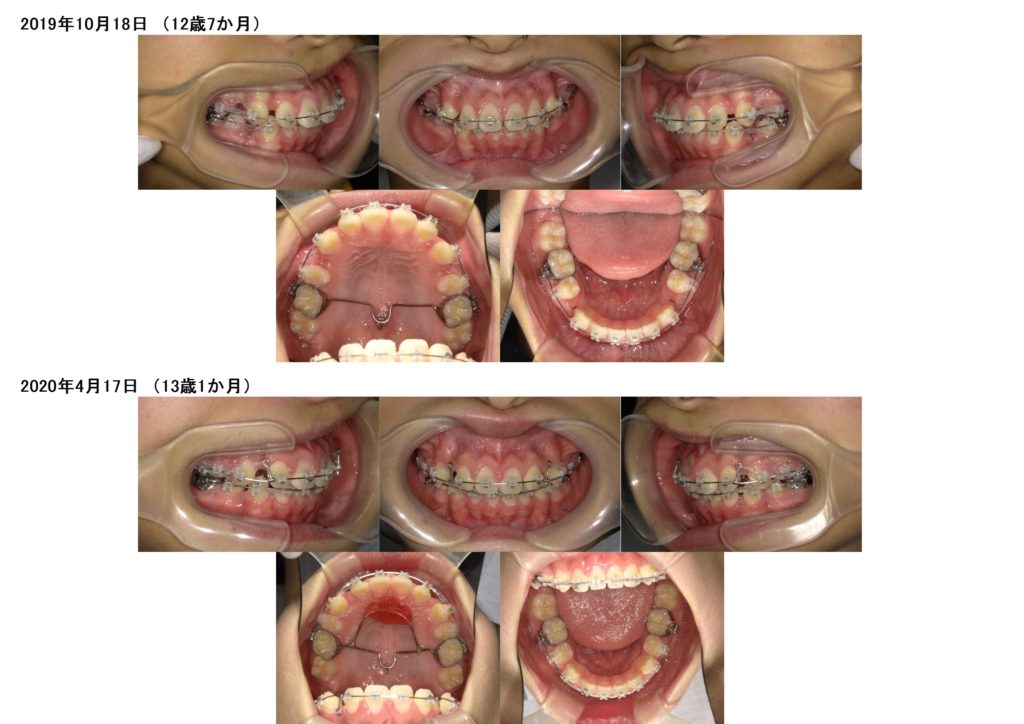

↑この患者様は上下の歯を2本ずつ抜歯しています。

上の顎にアンカースクリューを使用し、抜歯した際に6番目の歯が寄ってこないためにしています。

このように土台を整えつつ、ブラケットを使用し調整をしていきます。

奥歯の噛み合わせを確立したら、あとは前歯部の噛み合わせを合わせ引っ込めていきますよ

隙間が埋まったら治療が終わりです☆

↑治療前、治療後の口腔内写真の比較です。

上下の顎のアーチを整えながら、抜歯した隙間を利用し噛み合わせの深さや突出している部分も改善しているのが分かると思います。

約2年間のブラケット治療になりますが、お口の中もとても変化します。突出している方だと横顔のラインも変わりますので、